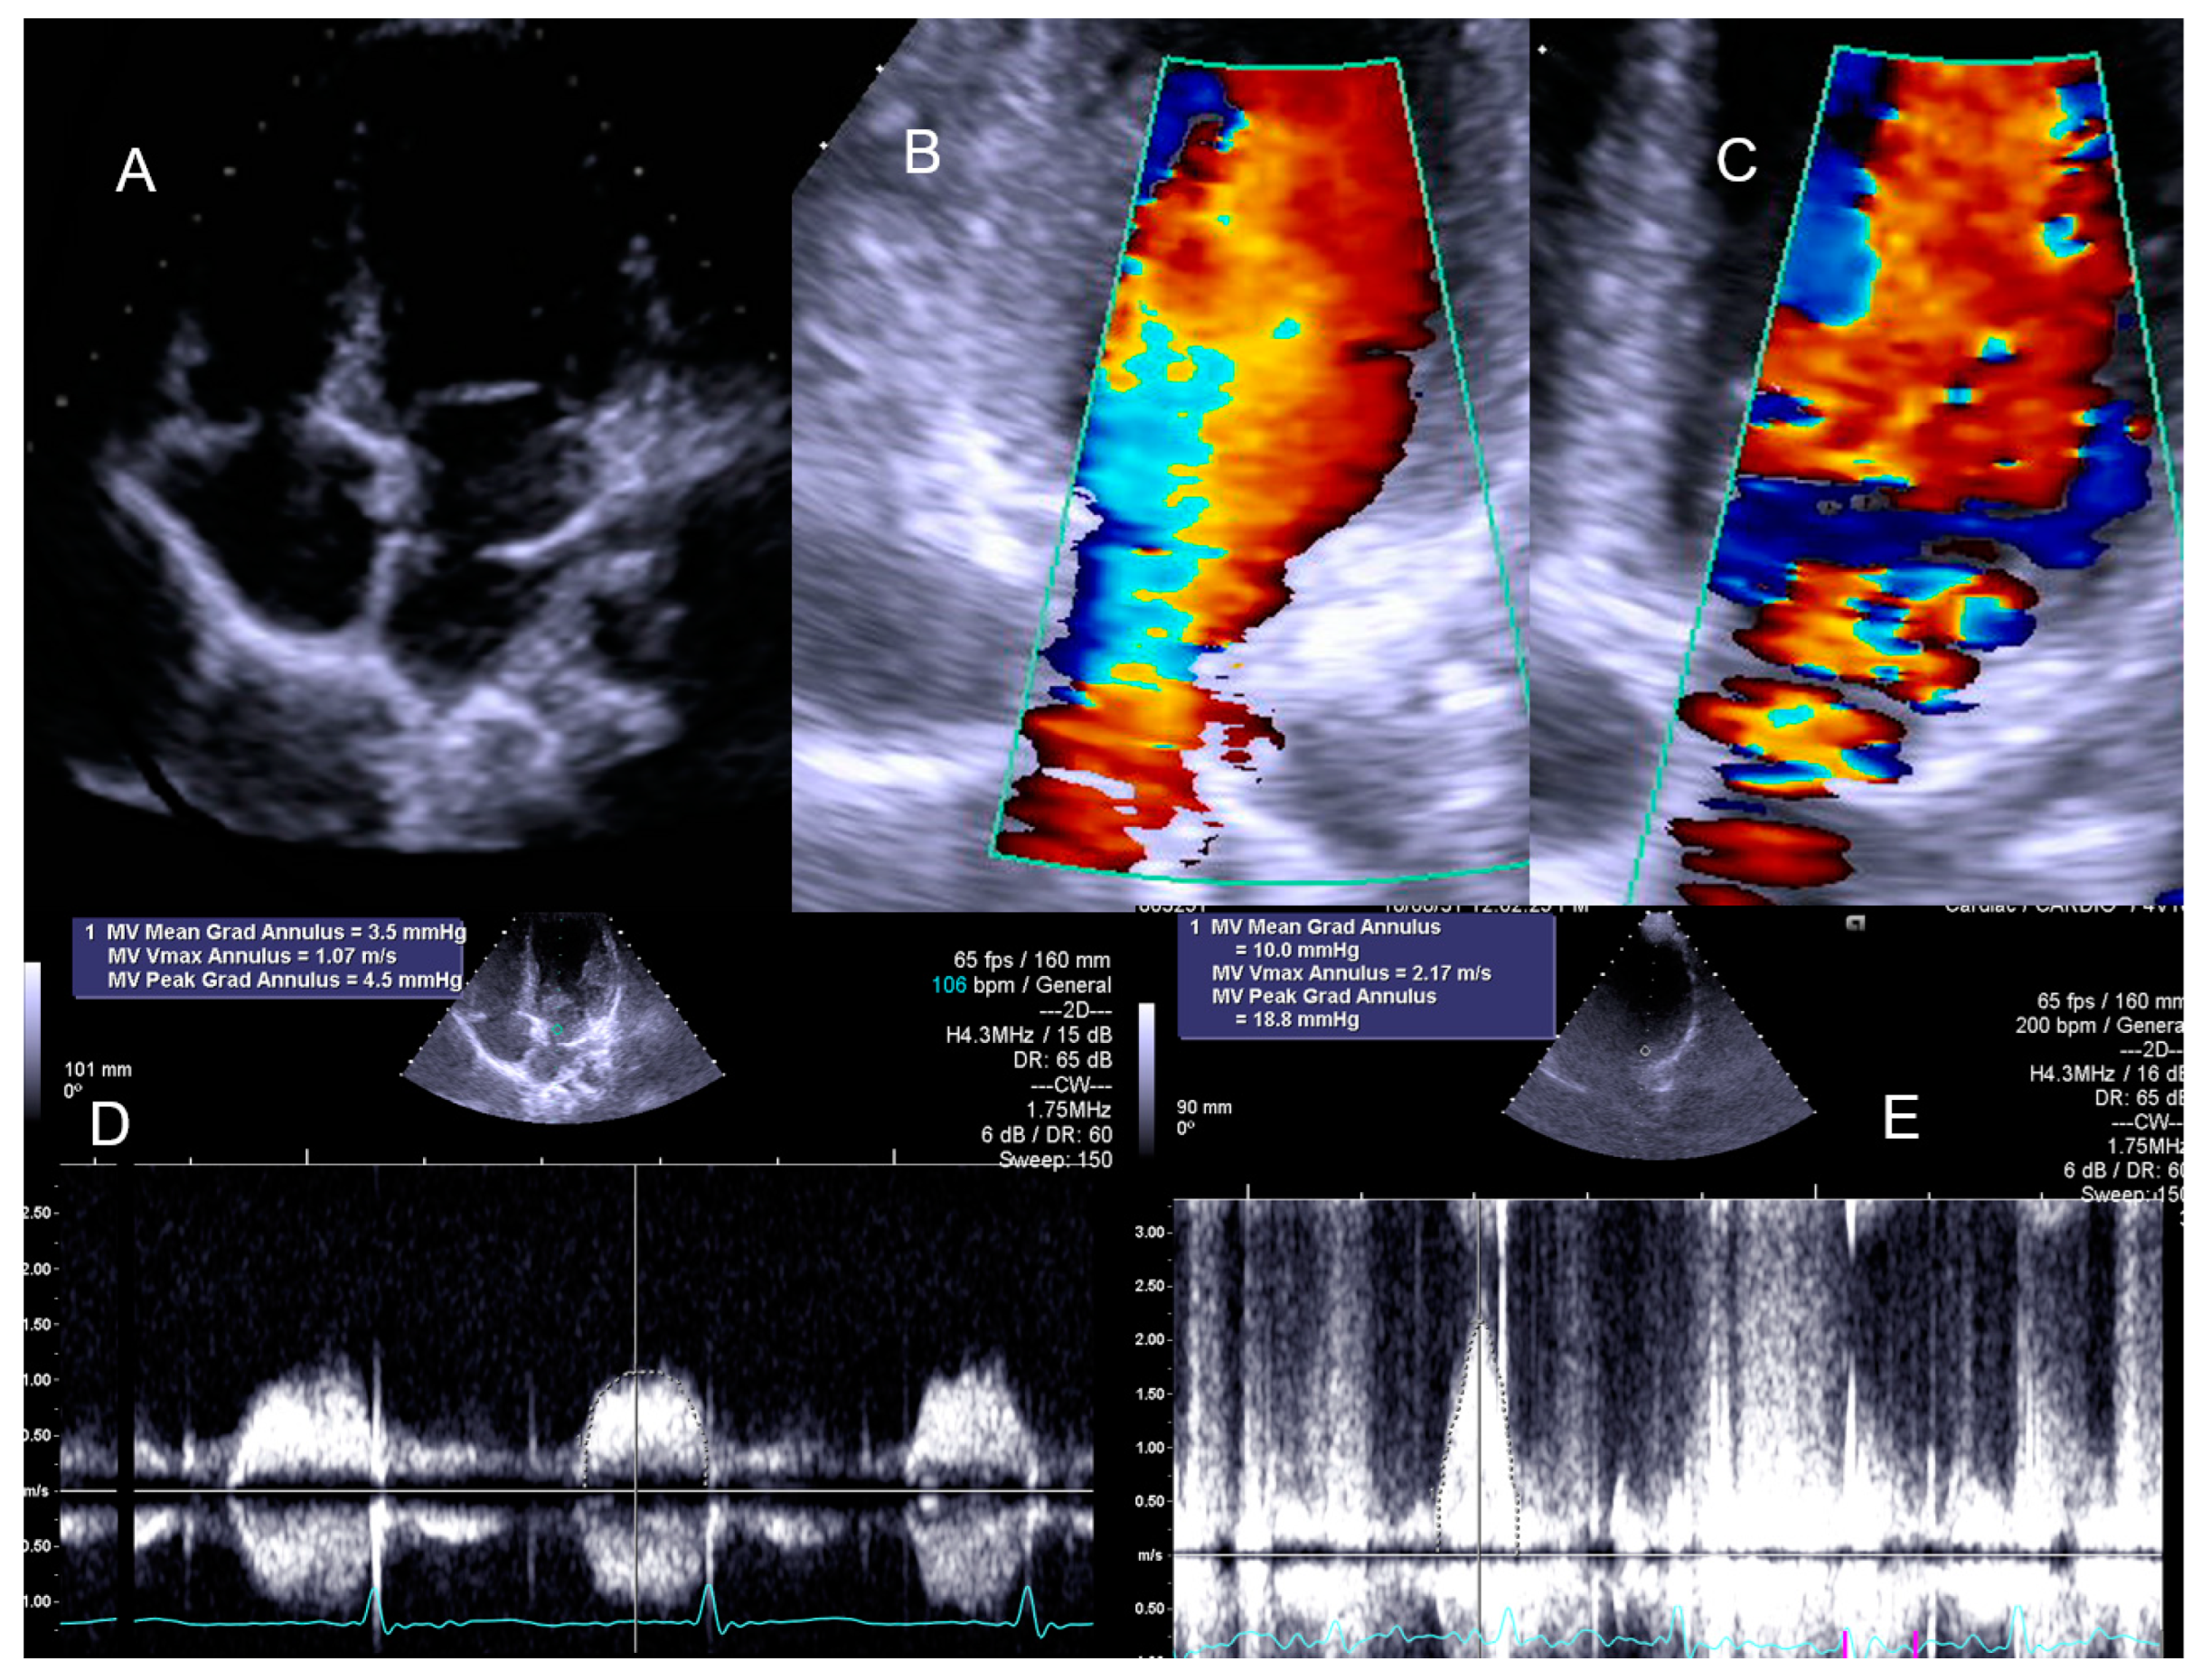

Figure 2.

Significant intraventricular gradient in a young boy with angina and ST alterations in the exercise stress test. He also developed systolic anterior movement (SAM) of the mitral valve [1].

The child with Cortriatriatum sinister revealed a nonsignificant increase in the diastolic mean gradient (Figure 8).

Figure 8.

The exercise Doppler data in conjunction with the exercise and clinical data led the medical team to keep the patient in close clinical follow-up. (A): Intra–atrial septum in “cortriatriatum”; (B): color flow before exercise; (C): color flow at peak exercise; (D): continuous–wave (CW) flow before exercise; (E): CW flow at peak exercise [1].